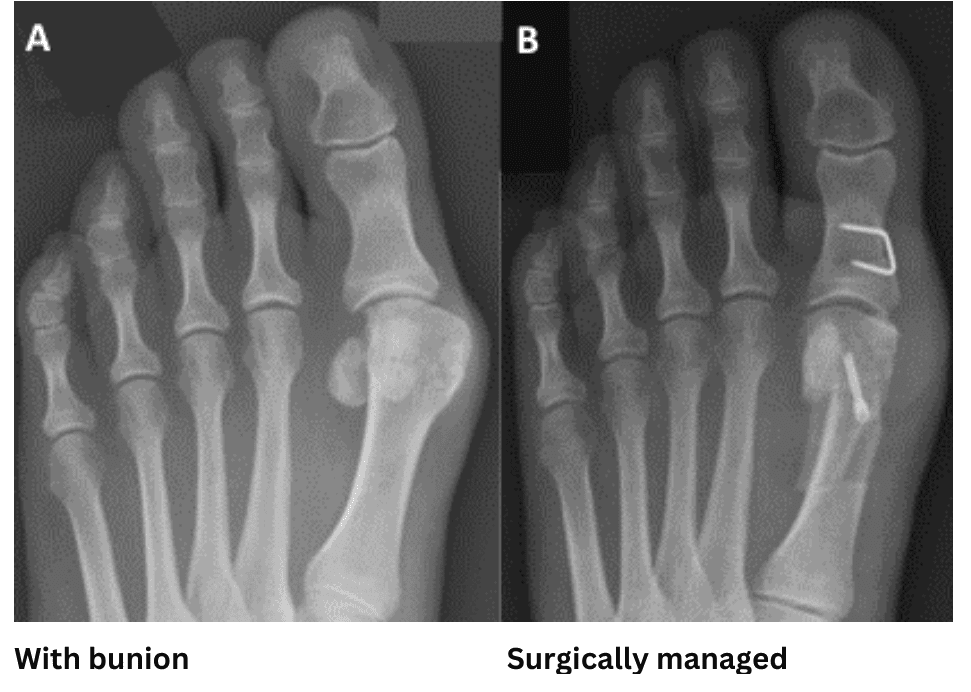

Hallux Valgus (bunion)

What is it?

Hallux valgus is the medical term for a bunion. It is the most common type of toe deformity and affects women much more than men. With a bunion, the big toe slowly becomes misaligned. It can occur on one or both feet and may or may not cause pain.

Surgery

Severe cases may be operated on, for example:

- the deformity will not fit any footwear

- the pain is very bad most of the time

- the toe position is causing other toe issues

- the bunion is stopping you from performing your job or other daily necessary functions.

There are many variations of surgery for bunions and a surgeon will need to evaluate you carefully to select the right approach. In most cases the surgeon will open the foot from the side and make carefully-angled incisions in the foot bones, to reposition them into alignment.

The surgeon will trim prominent bumps and insert screws to hold the bones in alignment. The screws stay in permanently.

Recovery will take at least 3 months, with 6 weeks of limited weight bearing

Risks include, making pain worse, infection, painful scar tissue, non-healing bones, poor correction, nerve damage and chronic pain syndrome. This would only be considered after all measures have been tried, often trying variations of them more than once.

Hallux Valgus (bunion) surgery

What is offered?

Hallux valgus, or ‘bunions’, may or may not cause pain. If there is no pain, no treatment is required. Mild pain and smaller deformity is managed without surgery.

Surgery is carried out to straighten the toe and reduce the prominence, effectively narrowing the foot. If you have other toe deformities that are painful, these will usually be dealt with at the same time. If you have two feet that need surgery, this may be done simultaneously or one after the other. This is a decision made in conjunction with the surgical team.